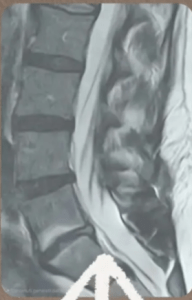

Supporto con QMR Therapy in ernia lombo-sacrale L5–S1